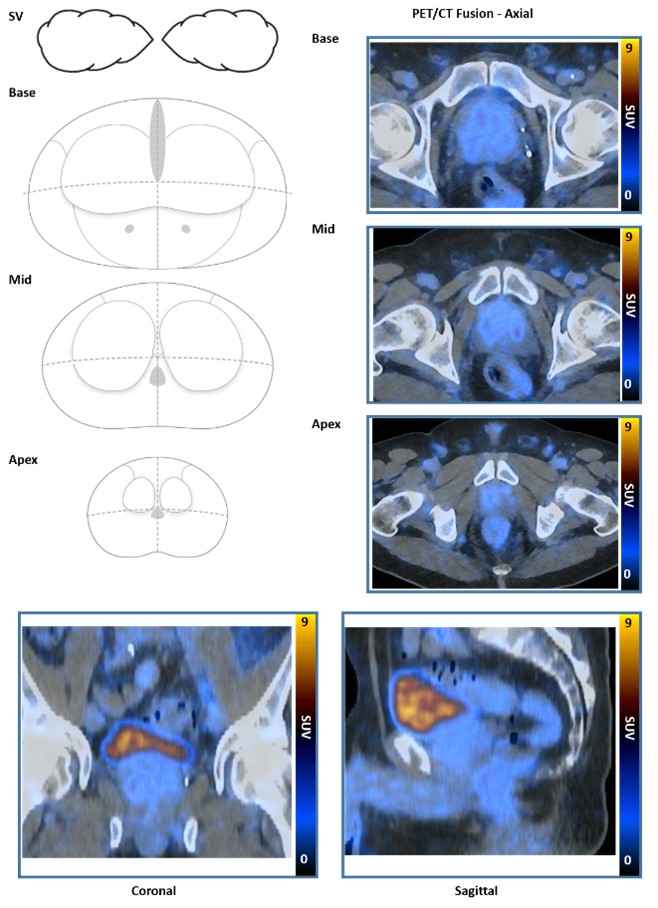

PRIMARY score

The PRIMARY score is a 5-category scale developed to identify clinically significant intraprostate malignancy (csPCa) on 68Ga-prostatespecific membrane antigen (PSMA) PET/CT (68Ga-PSMA PET) using a combination of anatomic site, pattern, and intensity.